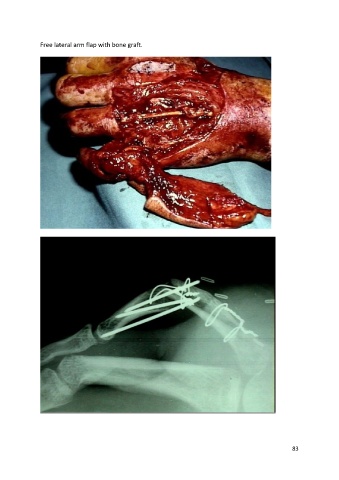

Free lateral arm flap with bone graft.